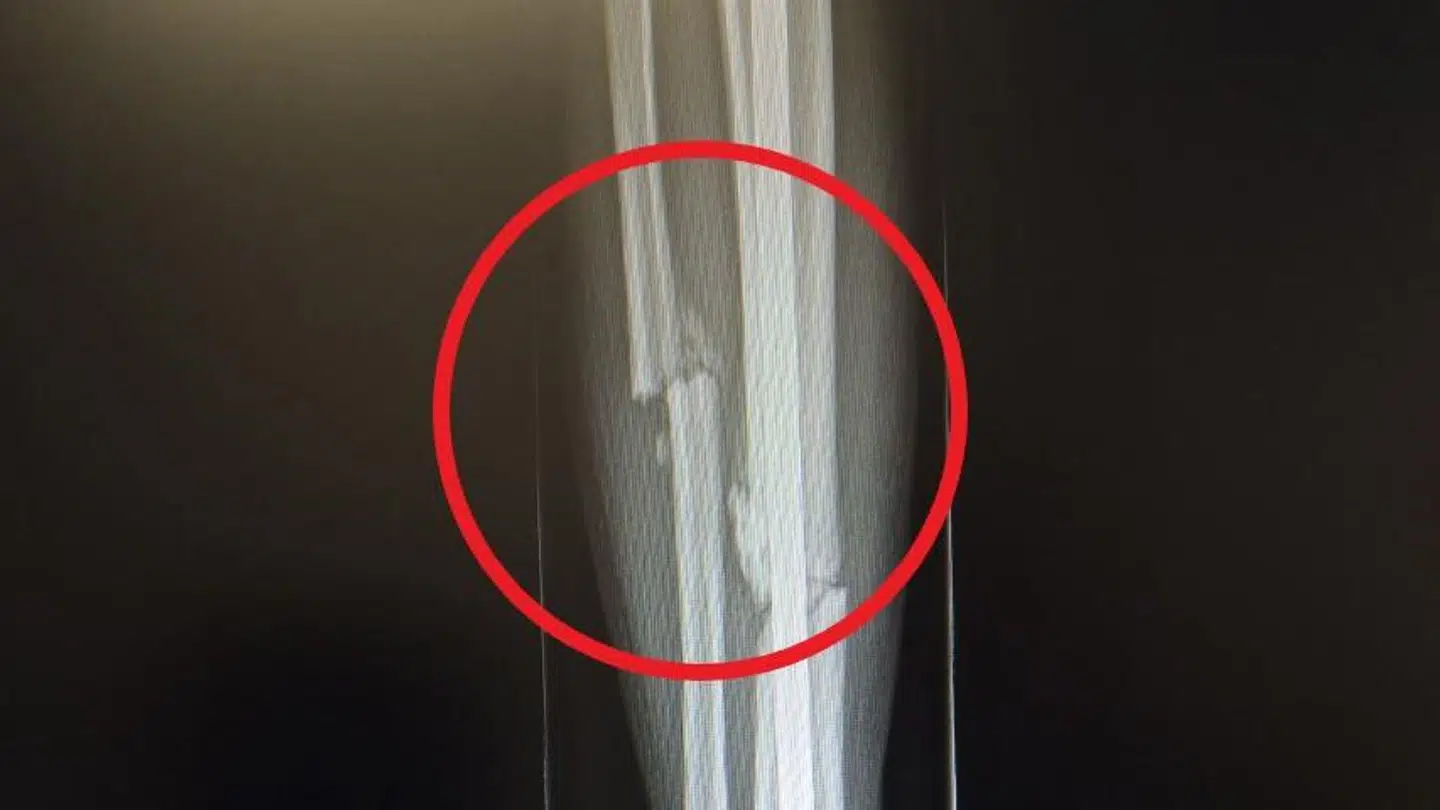

Det danske stortalent er i gang med genoptræningen efter en skrækulykke i december, hvor han brækkede benet, da han frontalt blev kørt ned under en cykeltur i Spanien.

»De efterfølgende uger gik godt, hvor jeg fik trænet og kørt rigtig stærkt på cyklen, men scanningerne har bare vist, at knoglen stadig er knækket, og helingen går ikke særlig godt, så jeg har måttet tage en pause fra det hele,« fortæller cykelrytteren om en tilværelse, hvor han i øjeblikket nærmest er helt isoleret fra omverdenen – dog ikke på grund af coronavirussen: